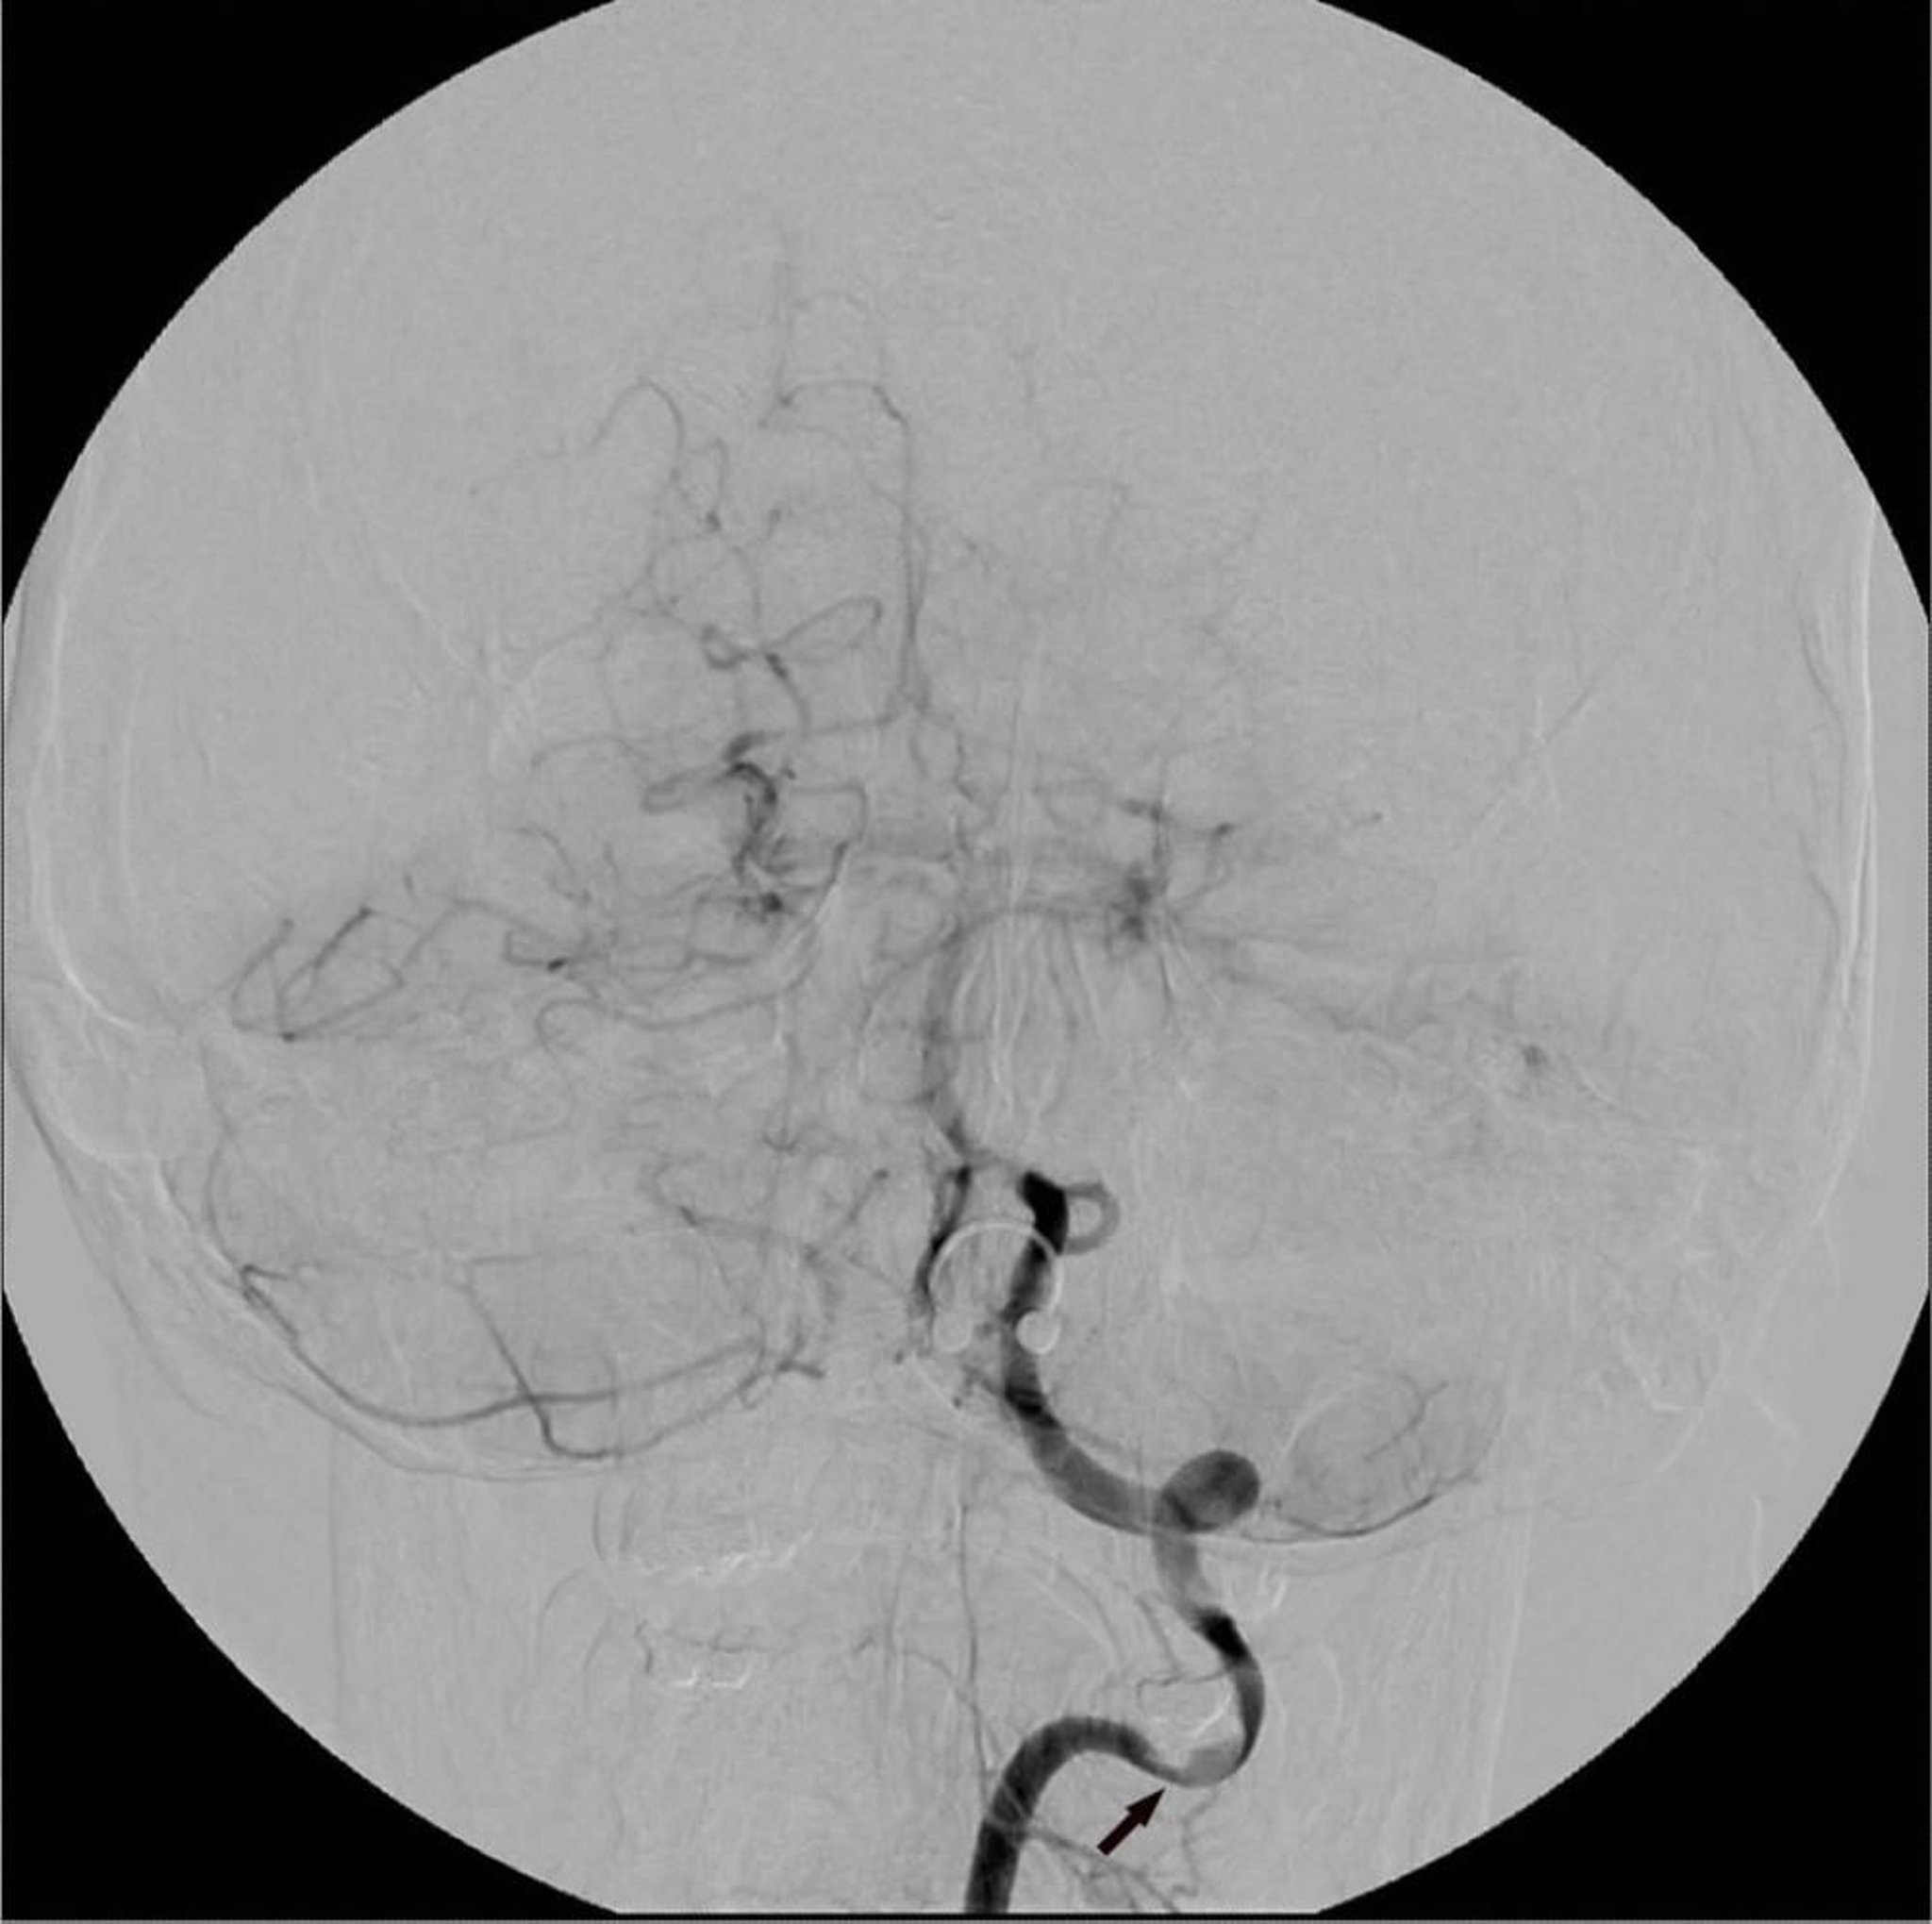

L'angiographie numérique à soustraction digitale de l'artère vertébrale gauche montre une zone de sténose focale (flèche).

Image courtoisie de Hakan Ilaslan, MD.